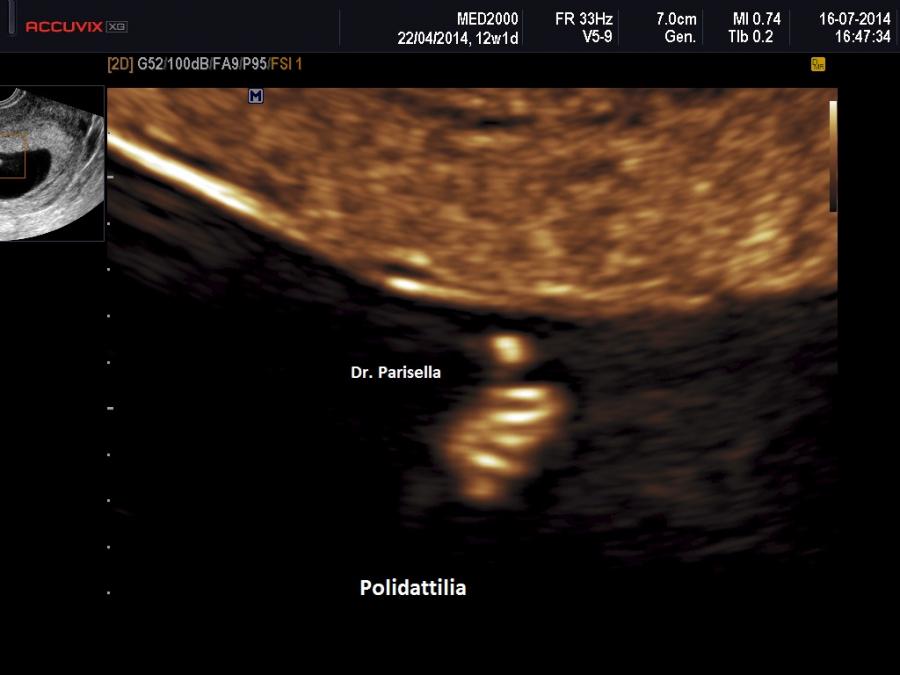

• Anomalie scheletriche: brachidattilia, sindattilia, polidattilia, clinodattilia del V dito;